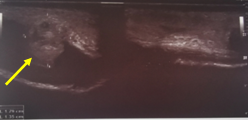

A 38 years old male patient presented to the hospital after hearing popping sound followed by asudden detumescence while having intercourse along with a profuse urethral bleeding, with no swelling or deformity of penis as shown in Figures 1&2. Local penile examination was unremarkable therefore,it was a bit misleading. Urethral catheter was inserted gently and carefully which drained clear urine andurethral injury was suspected. Patient was resuscitated and started on broad spectrum antibiotics as per the hospital`s protocol subsequently the patient had a considerableperiurethral bleeding that raised the suspicion of an additional underlying pathology; beyond the urethral injury. Ascending andmicturatingcystourethrogramin Figure 3 confirmed the presence of a tear in the tunica albuginea extending to the urethral lumen and draining the blood from the corpora cavernosa directly into the urethra, it did also show a normal filling of the anterior urethra with irregular extraurethral extravasation and finally a penile duplex ultrasound scan in Figure 4 confirmed the presence of multiple subtunical and bilateral extracorporeal small organized hematoma. Although the physical findings were not suggestive of a penile fracture, exploration was offered and advised to the patient in the view of the finding but unfortunately the patient refused to undergo exploration after settling of the urethral bleeding and he was fully and formally informed about the possibility of the associated risks mainly erectile dysfunction. The patient was self-discharged and represented 3 month later, with moderate degree of erectile dysfunction and examination revealed a 3 cm fibrotic plaque on ventral aspect of left corporeal body.

Figure 4 Duplex US showing presence of extracorporeal small organized hematoma (yellow arrow).